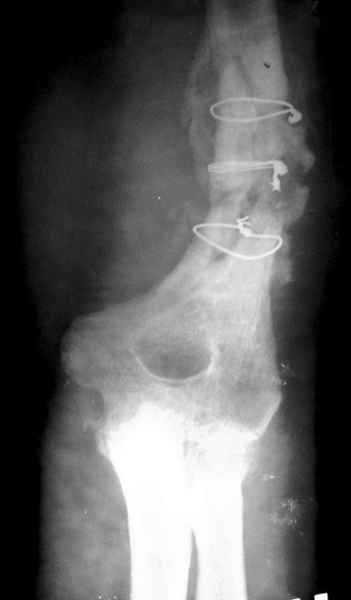

Второй случай, также после множественных операций:

пластина, аппарат, серкляж и парез нерва.

Также ревизия, из-за низкого состояния доступ был

сделан через остеотомию локтевого отростка.

Ложный сустав фиксирован двумя локинг плейт с

аутокостной пластикой, также через два месяца увидели признаки консолидации.

Движение в суставе разрешили в две недели.